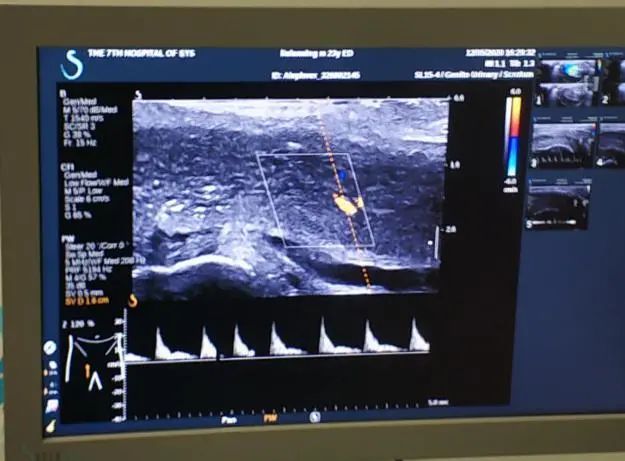

但现在,广大男同胞有福了。中山七院男科联合超声科已开展阴茎海绵体注射血管活*药性**物(ICI)后阴茎彩色多普勒超声(CDFI)结合阴茎硬度分级与海绵体组织弹力指数检查。该检查能够较准确地反映阴茎血流动力学改变,为各种勃起功能障碍诊断提供客观依据,目前该检查是诊断血管性ED最有价值的方法之一,被认为是诊断动脉性勃起功能障碍的金标准。

阴茎彩超(CDFI)检查

该技术由我院男科与国家辅助生殖与优生工程技术研究中心联合开展,现已证实CDFI检查是男性勃起功能障碍诊断最有价值的检查手段之一。我院男科玄绪军主任联合超声科林惠通副主任医师开展彩超下阴茎海绵体的弹力指数测定与勃起硬度的相关临床应用,该技术有望在完善勃起功能障碍的影像学诊断及分度、临床选择最佳的治疗措施方面提供技术支持,目前该项技术在珠三角地区率先开展。